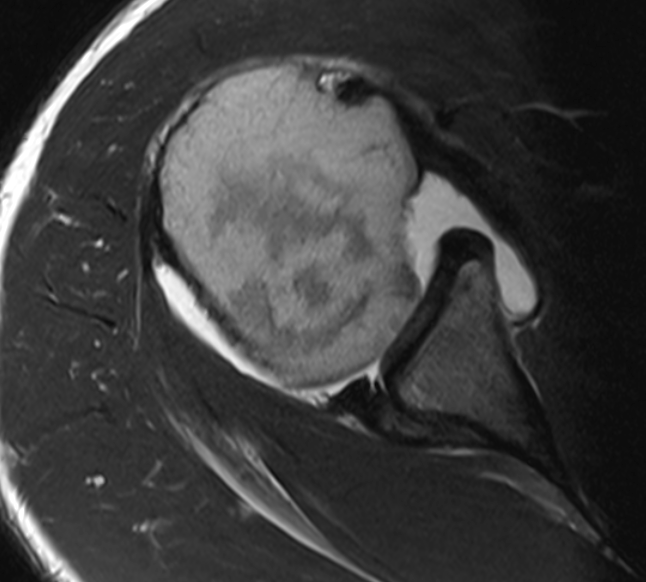

3. Posterior glenoid labral tear